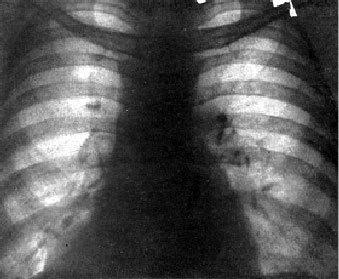

По данным обследования обращает внимание лейкоцитоз 18,1, при рентгеноскопии органов грудной клетки (рис. 1) деформация легочного рисунка, пневмония в нижней доле правого легкого, сердце расширено в обе стороны.

Рис. 1. Рентгенограмма больного Ю. 78 лет